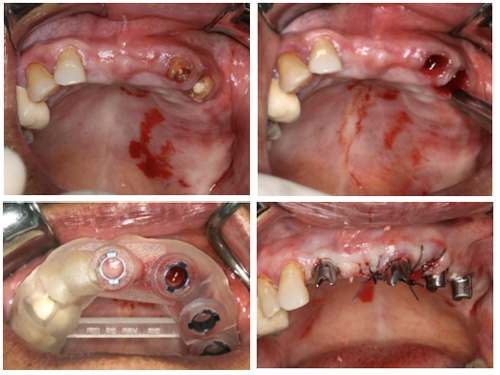

2.即刻种植

数字化口腔种植技术的优势与传统种植技术相比,在导板的帮助下,根据术前的方案规划和术中导板的精确定位,拔牙和种植可在一次手术中完成,种植位置、角度和深度都得到精确控制,实现微创手术、减轻患者痛苦。根据术前的合理规划和术中导板的精确定位,最大限度减小手术创伤、实现微创手术,降低术后肿胀、疼痛、感染等并发症的发生风险。